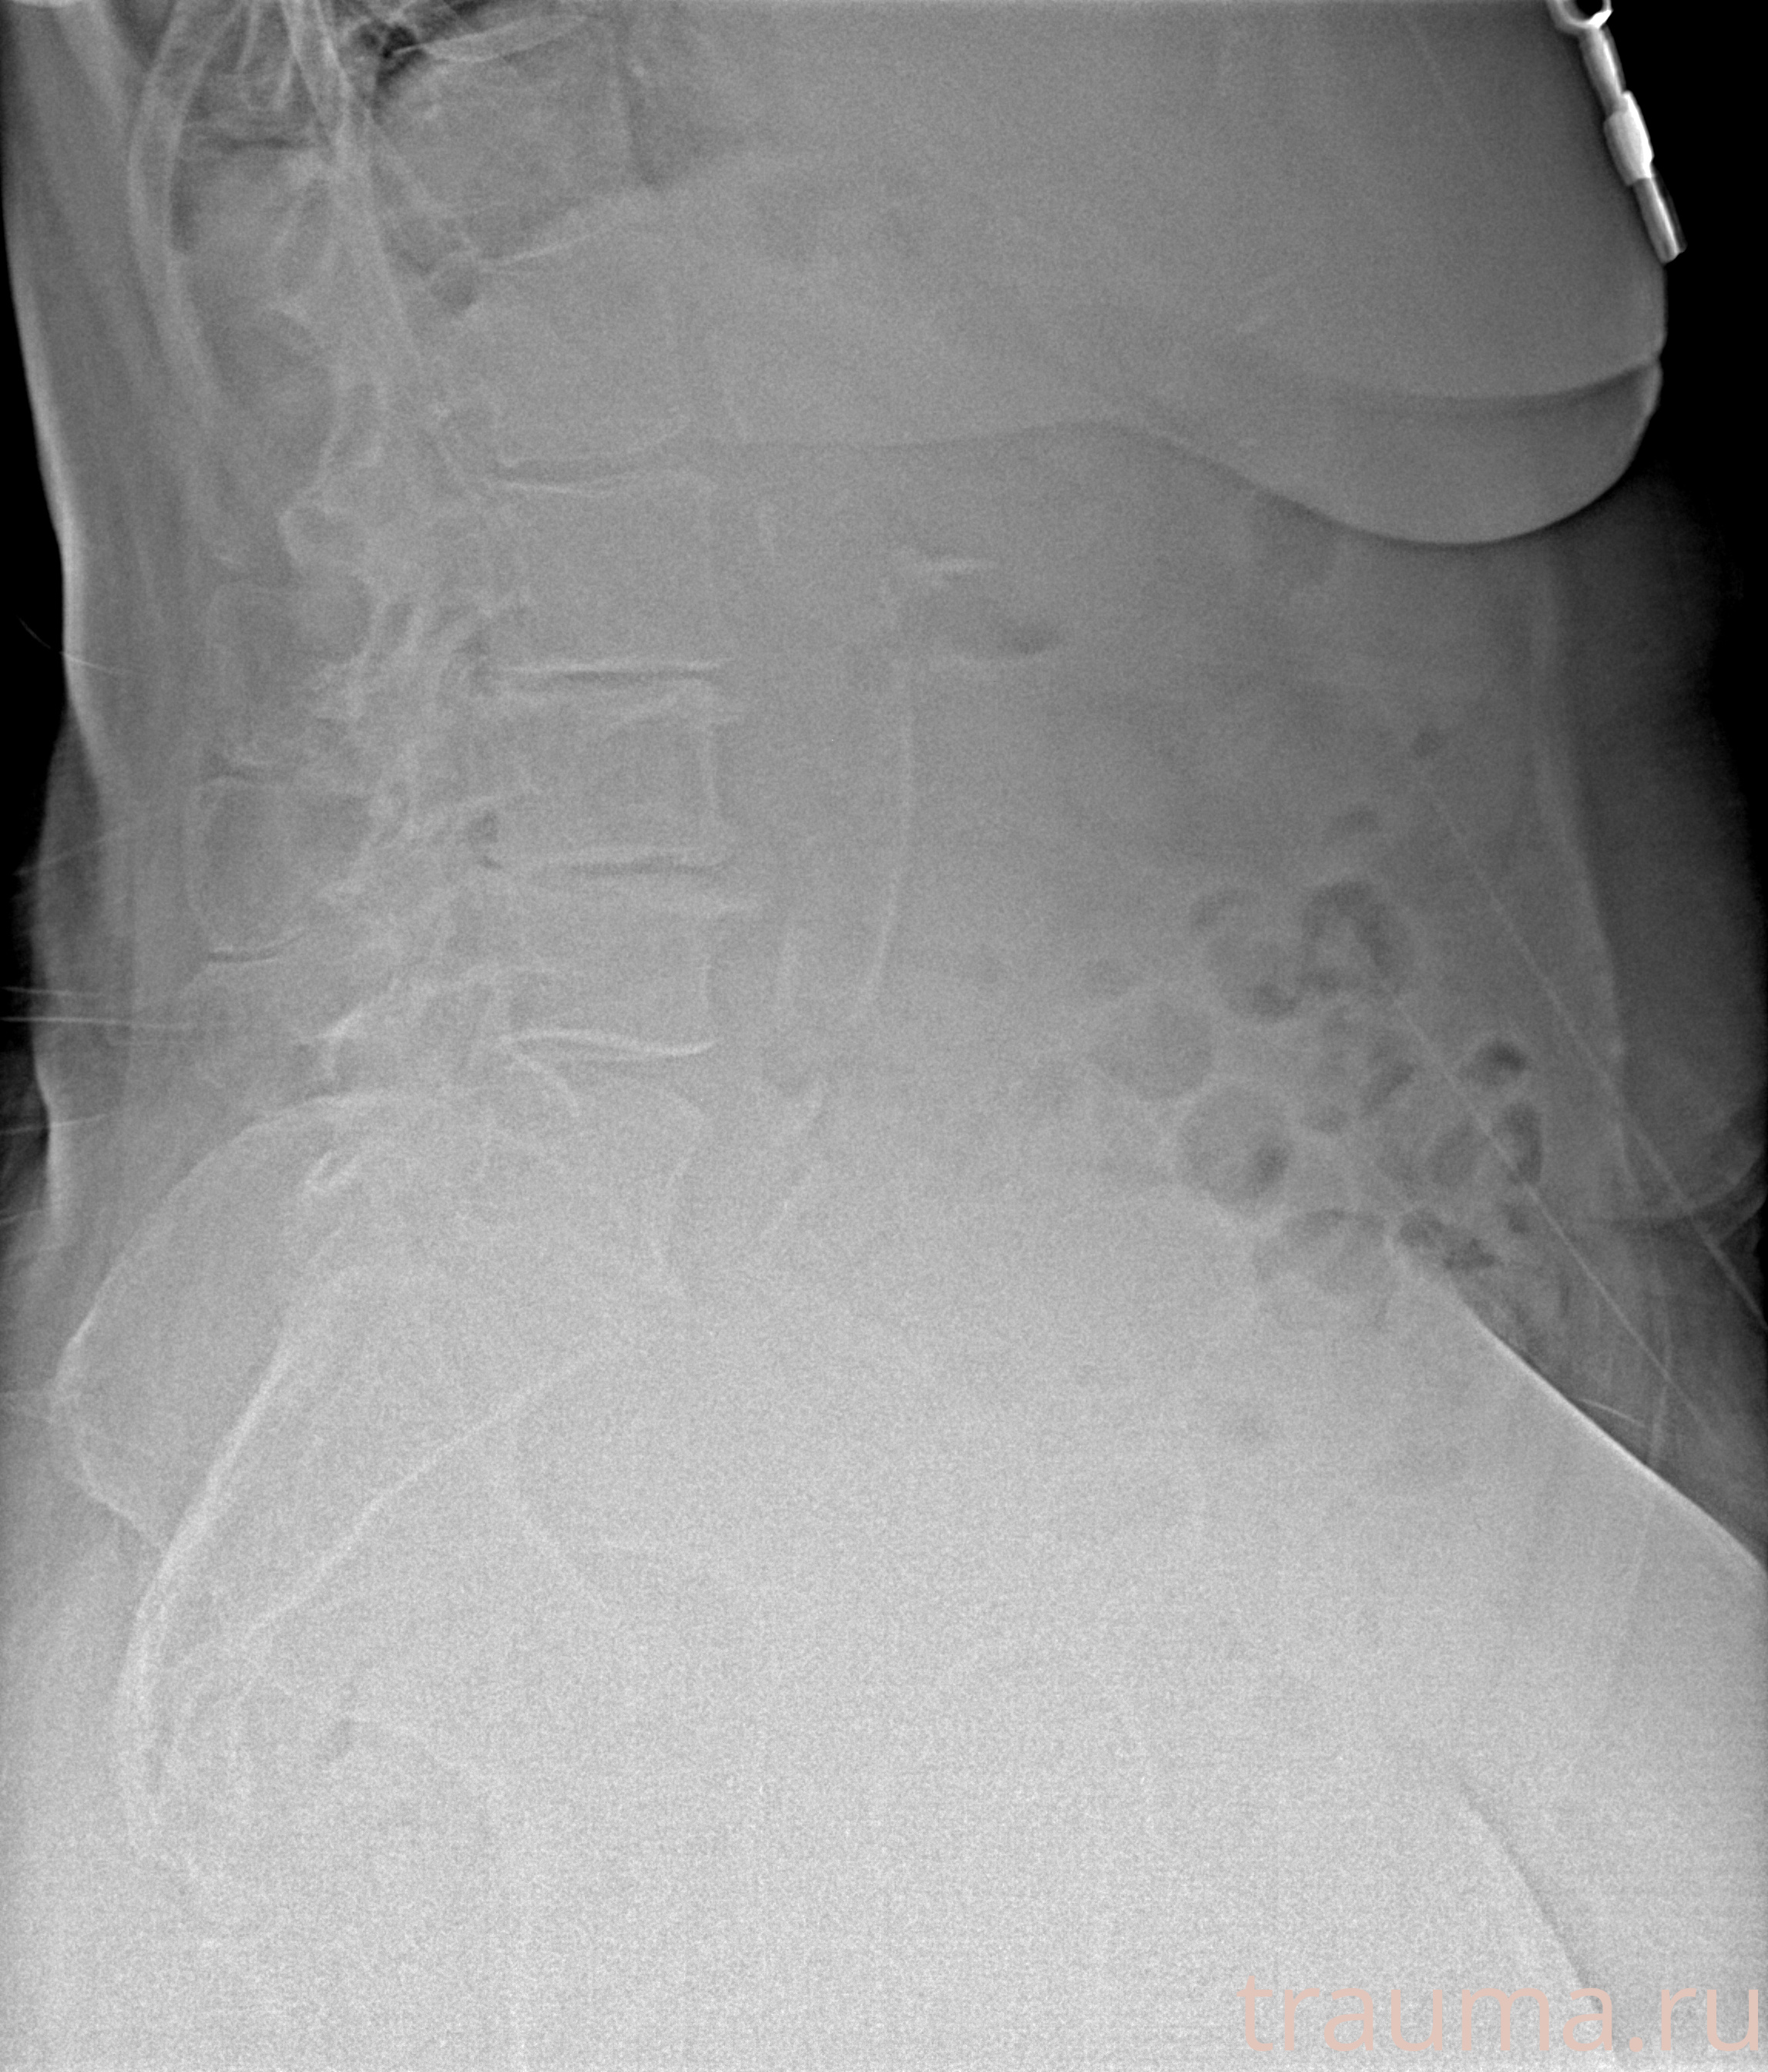

Рентген на дому: по вашему адресу приезжает врач-рентгенолог, травматолог-ортопед с мобильным рентгеновским аппаратом, проводит диагностику травмы или заболевания, делает необходимые рентгенограммы, дает рекомендации по дальнейшему лечению. Получить качественные снимки в домашних условиях возможно благодаря уникальной методике, разработанной МосРентген Центром для института  Склифосовского

при переломе шейки бедра и пневмонии от компании МосРентген Центр - партнера Института имени Склифосовского